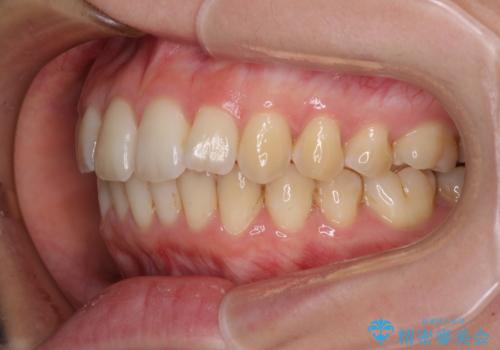

- 上下前歯のデコボコと深い咬み合わせを気にして来院された患者様です。

インビザラインによる上下歯列の拡大と、IPR(歯と歯の間を削る)にるスペースの獲得により、前歯のデコボコを改善することとしました。

上の前歯をもう少し整えたかったのですが、患者様の治療を早く終了させたいという希望により、細かい叢生を残しての終了となりました。